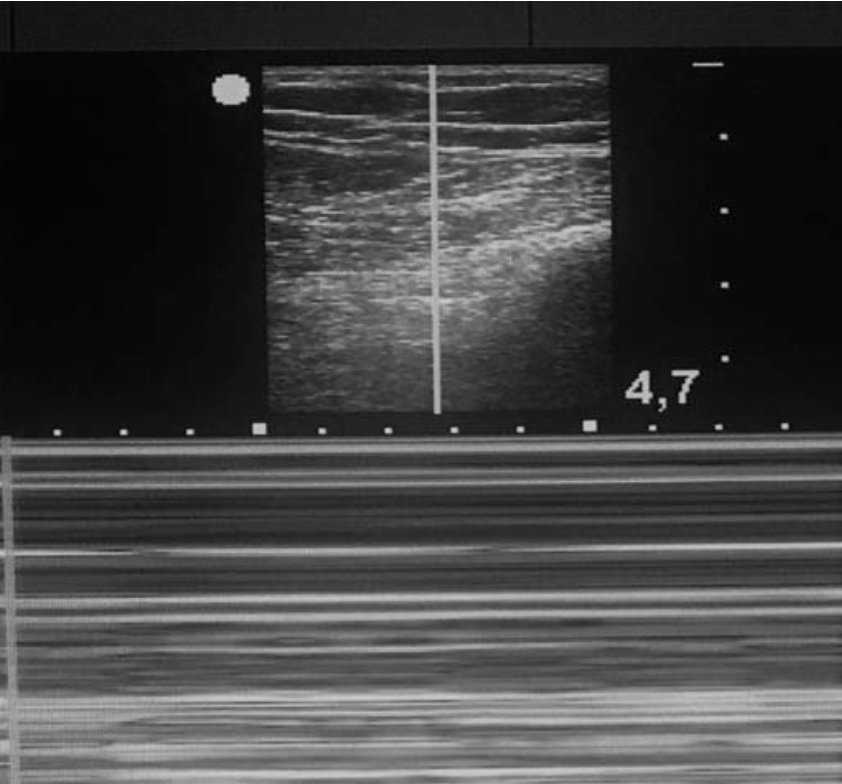

气胸在二维超声上表现为胸膜滑动征及 B 线消失,胸膜线变为带状低回声,混响伪像增多。

在 M 型超声上,正常的胸膜滑动征表现为「沙滩征」,气胸时则变为「条码征」(图 3),但以「肺点征」对气胸的特异性最大,可达 100%。所谓「肺点征」是指「沙滩征」与「条码征」相互过渡的区域(图4)。